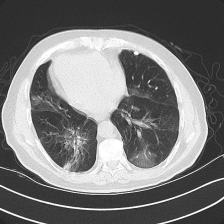

The four visualized examples in Figure 6 are from the binary segmentation experiments of Dataset_2. The first example shows a case in which infection has spread to both lungs and appears as a GGO and small consolidation region at the bottom of the right lung. The comparison between the Unet++ mask and the ground truth (GT) shows that the Unet++ architecture fails in segmenting most of the infection regions. The CopleNet, MISSFormer and UCTransNet masks show improved segmentation performance compared to Unet++. However, these architectures still miss some infected regions or segment lung tissues as infection instead. The mask of our proposed approach shows high similarity with GT in term of the number of regions and their global shape. Both examples 2 and 3 are cases where the infection has a peripheral distribution. The visualized masks show that the proposed D-TrAttUnet is the best architecture consistent with the ground truth. The fourth example depicts a severe case where the infection has spread to most of the lung regions. The visualized masks exhibit that our proposed architecture performs better than the comparison architectures.

Refer to caption Refer to caption Refer to caption Refer to caption Refer to caption Refer to caption Refer to caption

Slice Unet++ CopleNet MISSFormer UCTransNet D-TrAttUnet GT

Figure 6: Visual comparison of a segmentation model trained with different segmentation architectures for Binary Covid-19 segmentation using Dataset_2 and Dataset_3.